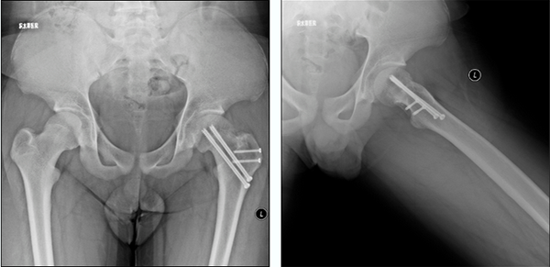

病例1 男,13岁,左侧重度SCFE

病例1 髋关节外科脱位,改良Dunn截骨,术后2年,X线示位置良好,无股骨头缺血坏死

1998年,北京积水潭医院小儿骨科在国内首先报道使用Russell牵引结合内固定治疗股骨头骺滑脱,在文中提出“对于急性滑脱,持续牵引逐渐内旋复位是可能的”;2012年开始应用髋关节外科脱位改良Dunn截骨来治疗重度SCFE;2018年在前期工作的基础上,开展应用股骨头骺内血供监测来实时监控术中股骨头骺血供;2019年开始应用在机器人辅助下行重度SCFE的经皮螺钉固定,并承担北京市医管中心专项项目:中重度股骨头骺滑脱治疗的临床研究。